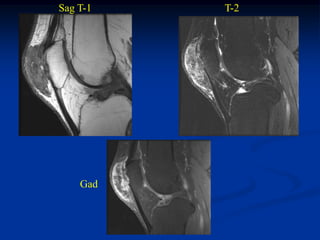

Case #1.1           Primary Hyperparathroidism

2008

56 year female with anterior knee pain for 2 years

Sag T-2   PD FS

Axial PD FS   Cor PD FS

2009                              2011

Two new aneurysmal lesions in foot two years apart

with bone graft to 3rd metatarsal ABC in 2009

2011

Osteomalacic looking bones